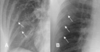

Q

Dato clave del patrón de consolidación alveolar